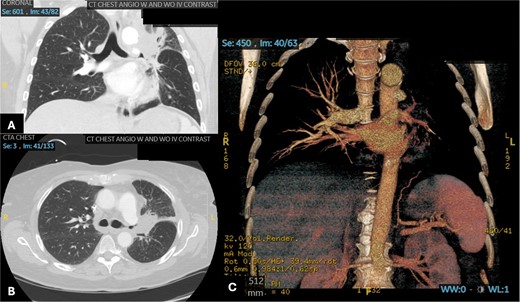

After 2 days, a follow-up chest X-ray showed a more prominent-appearing lung mass, prompting the ordering of a chest computed tomography (CT) scan. The CT scan revealed a focal mass-like consolidation measuring 2.4 × 2.2 cm in the LUL (Fig. 1A). Further infectious work-up including fungal antigen markers for Aspergillus, histoplasmosis, and blastomycosis were negative. His COVID-19 symptoms improved, so he was discharged home with close follow-up.

Patient 1 pre-operative images showing rapid progression of disease. (A) Initial CT scan with a 2.4 cm LUL pulmonary nodule. (B) Repeat CT scan 28 days later showing rapid growth and cavitation of the mass, now measuring 7.1 cm.

The patient returned with hypotension, weakness, and a presyncopal episode secondary to Clostridium difficile infection and dehydration. Chest imaging showed further growth of the LUL mass now up to 7.1 cm with cavitation from 4 weeks earlier (Fig. 1B). A flexible bronchoscopy was performed and samples sent for pathology and microbiology. This revealed extensive tissue necrosis and fungal hyphae consistent with mucormycosis.